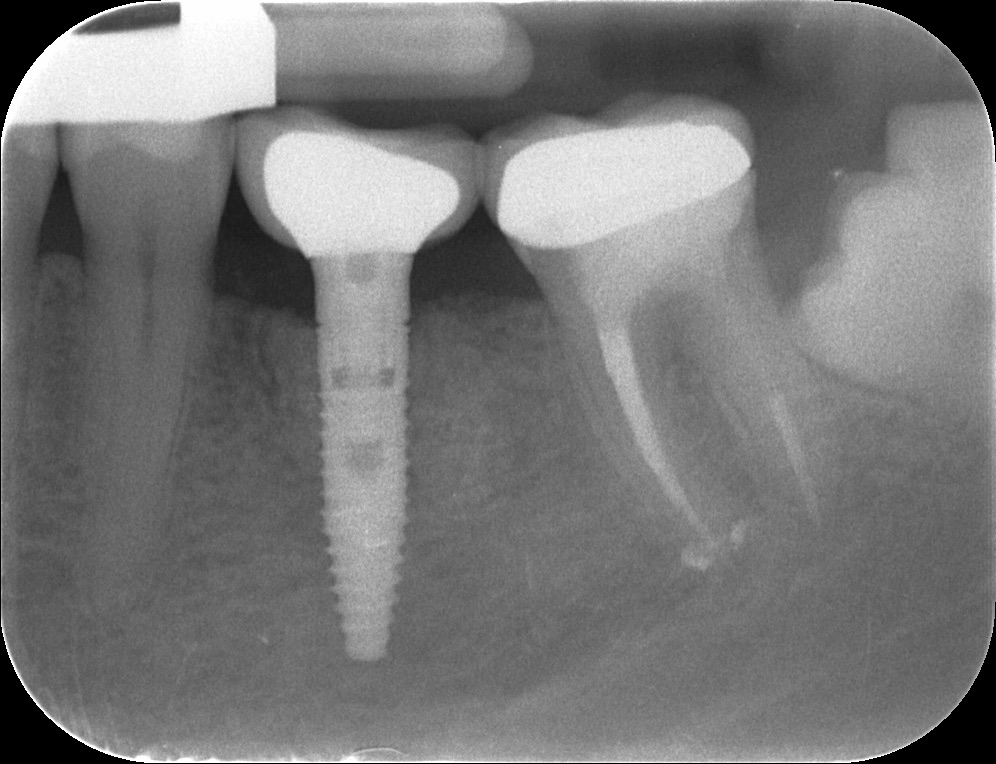

Pani Malwina z Chorzowa zgłosiła się z powodu stanu zapalnego w dolnym zębie trzonowym, ze względu na zaawansowanie procesu niemożliwie było uratowanie zęba i podjęto decyzję o jego usunięciu. Żeby zabezpieczyć kość pod planowany w przyszłości implant bezpośrednio po usunięciu zęba zregenerowano kość biomateriałem, aby potem wykonać zabieg implantacji i bezpiecznie posadowić koronę na implancie. Dzięki wykonanej regeneracji kości w dentestica Katowice podłoże kostne pod implant jest stabilne i zapewnia prawidłowe, długofalowe funkcjonowanie odbudowy na implancie. Bardzo ważne jest aby usuwać z organizmu stany zapalne i jednocześnie planować odbudowę podparcia kostnego pod przyszłe zęby, ponieważ brak nawet pojedynczego zęba zaburza funkcję całej jamy ustnej.